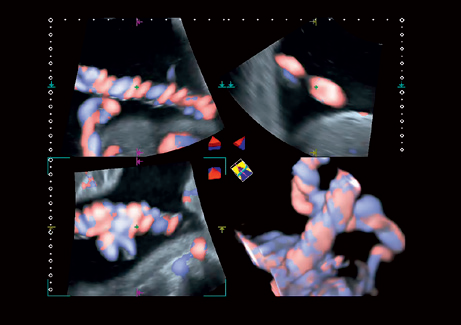

• 3D Color - цветное 3-х мерное изображение

• STIC Color - цветная объёмная визуализация сердца плода

• Трехмерная эхография в реальном времени с использованием специализированных 4D датчиков;

• Программа анализа сердца плода в трех проекциях в реальном времени 4D Stick;